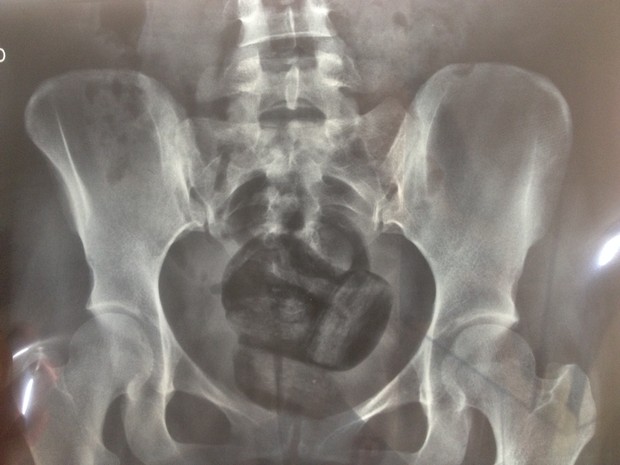

Manaus – Uma mulher, identificada como Regina Paula Costa Abreu, foi detida, na manhã deste sábado (27), ao tentar entrar com drogas e dinheiro, escondidos nas partes íntimas, na Unidade Prisional do Puraquequara (UPP), na Zona Leste de Manaus.

De acordo com a Secretaria de Estado de Administração Penitenciária (Seap), o flagrante ocorreu por volta das 11h, durante o procedimento de revista. Foram encontradas uma porção de maconha, uma pedra, supostamente, de cocaína, e a quantia de R$ 30 em espécie. Todo o material estava nas partes íntimas da mulher.